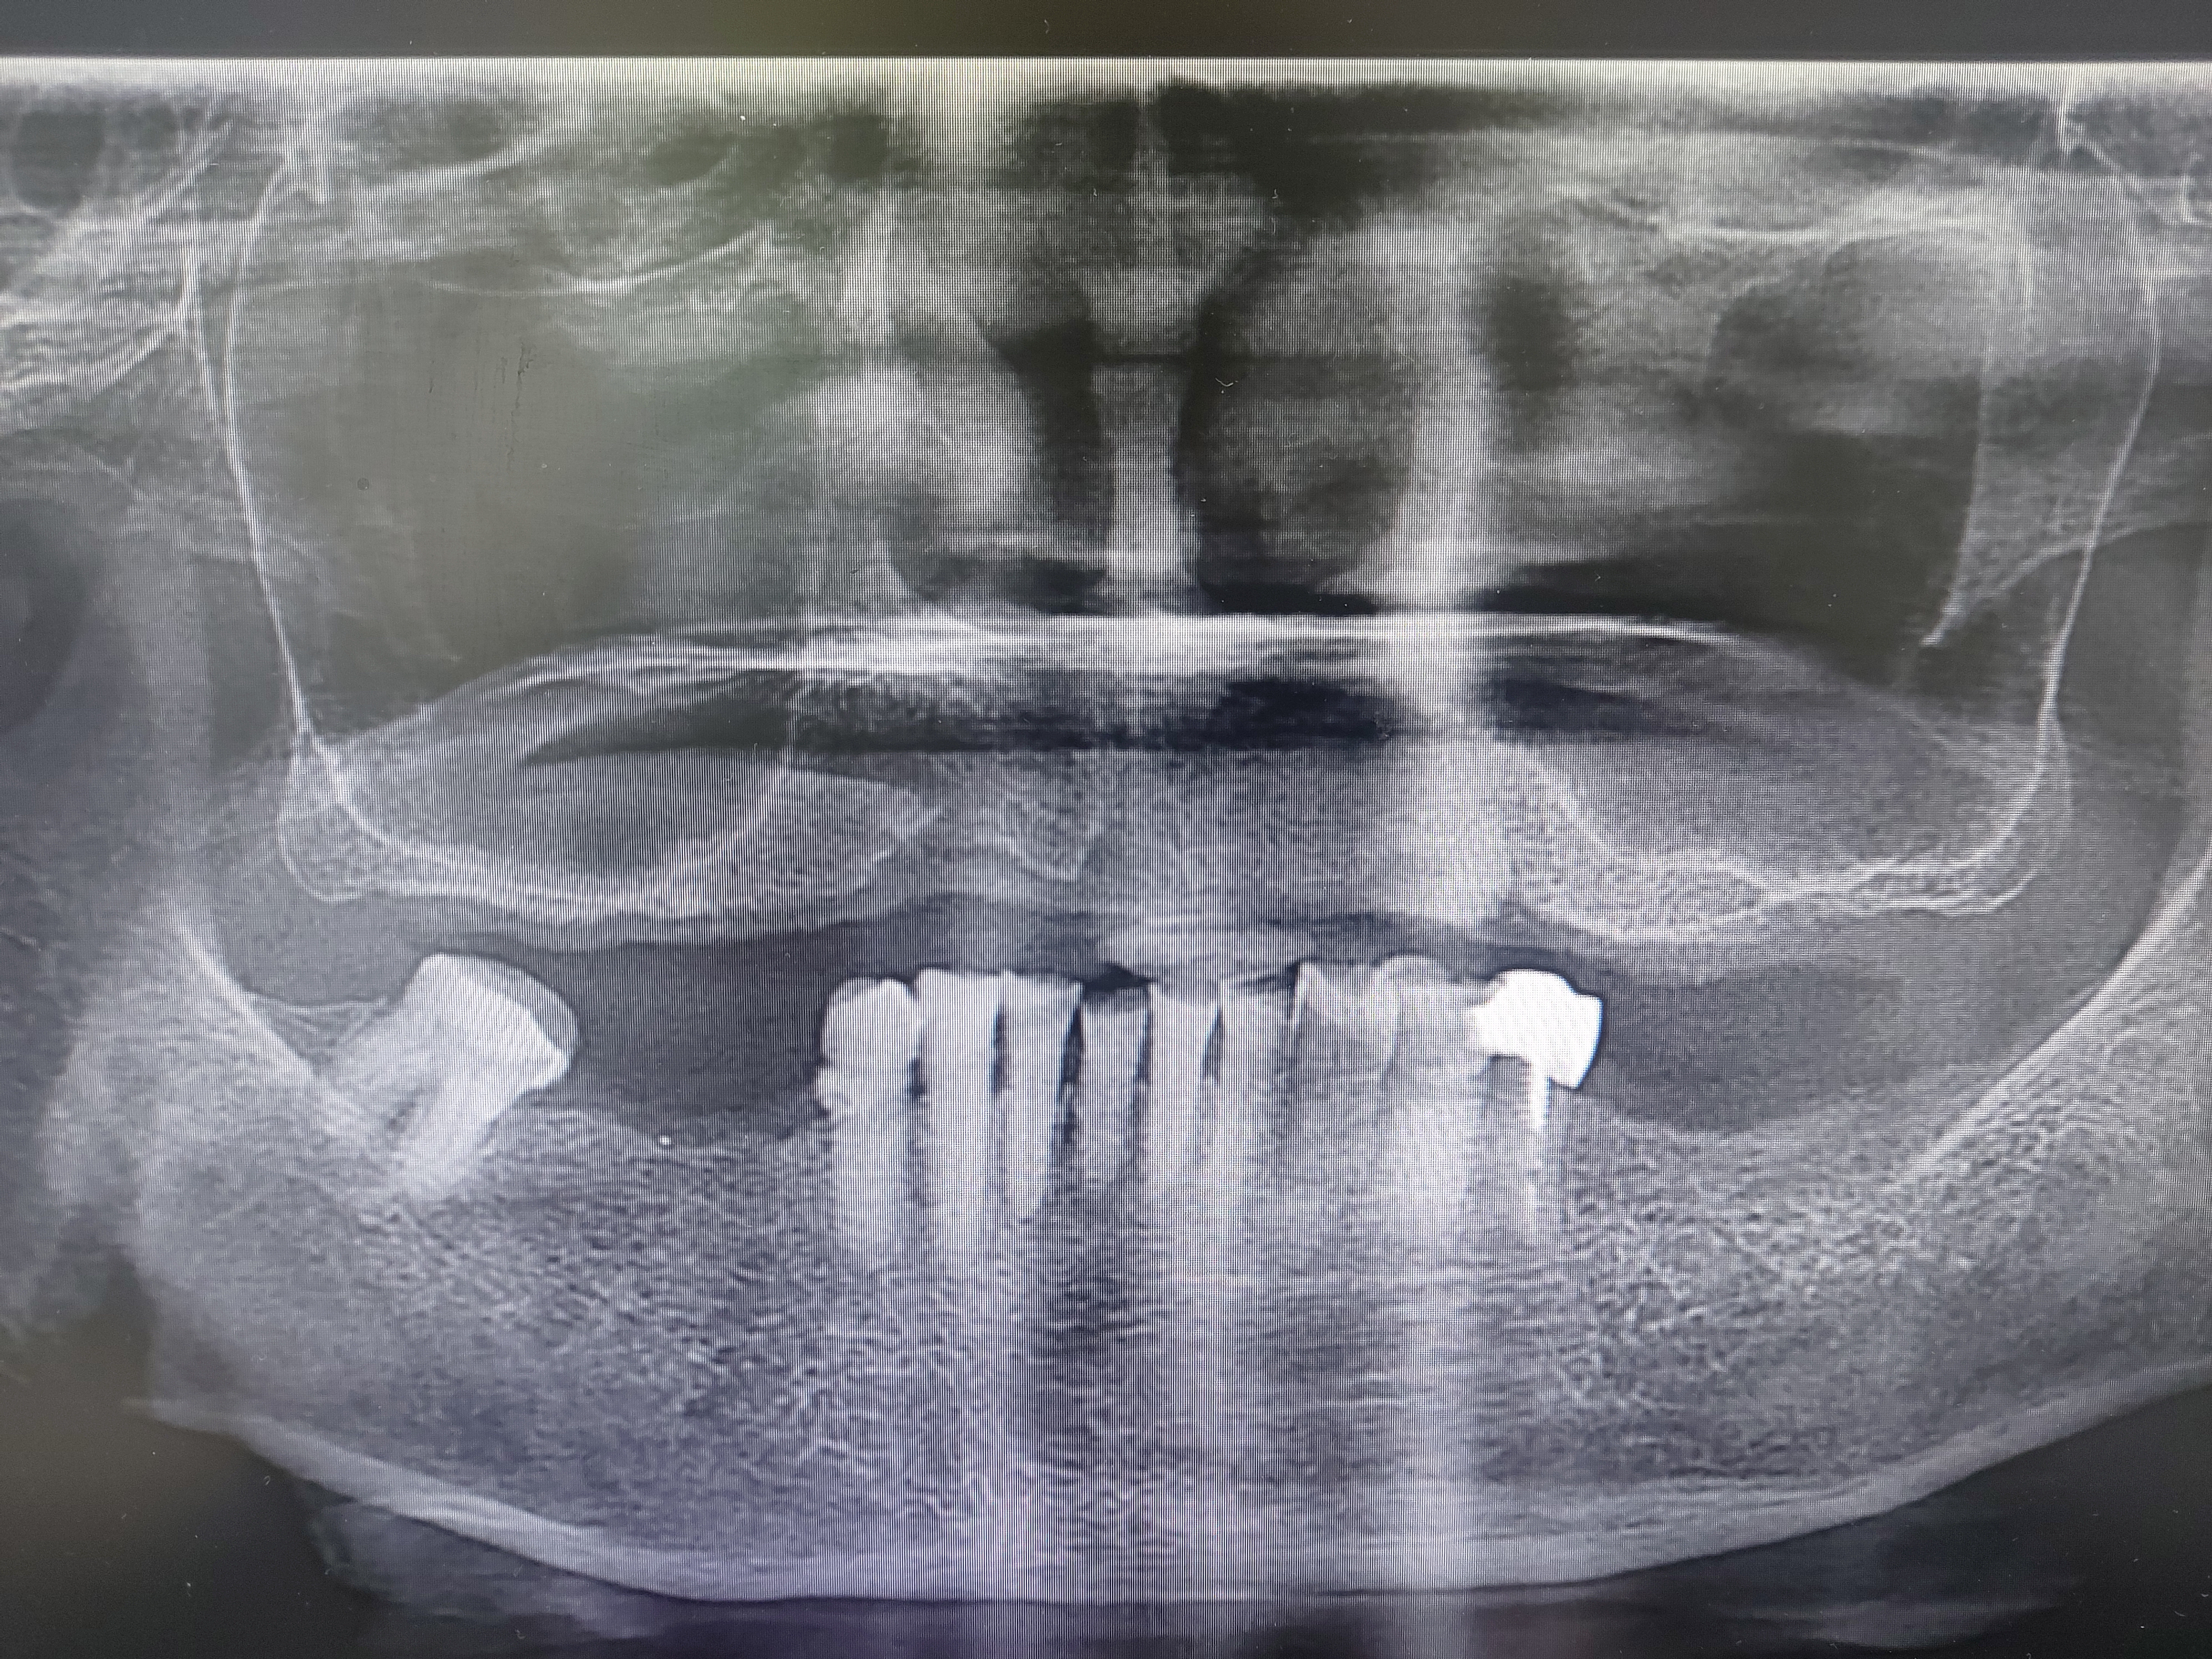

상악동이 아랫쪽으로 내려오면 치조골의 높이가 부족해집니다. 임플란트를 식립할 만큼의 뼈가 부족해지기 때문에 내려앉은 상악동의 점막을 들어올려서 그 공간속에 뼈를 넣는 다음

임플란트를 식립하게 됩니다.

기본적으로 임플란트를 식립할 경우 최소 8~ 10 mm정도의 뼈가 필요하며 잔존골의 높이에다가 부족한 만큼 뼈를 이식하게 됩니다.